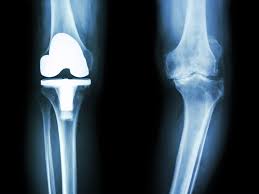

무릎 인공관절 수술, 왜 필요한가요?

무릎관절은 체중을 가장 많이 지탱하는 관절입니다. 나이가 들수록 연골은 점차 마모되고, 충격을 흡수하는 능력도 감소합니다. 이로 인해 통증, 뻣뻣함, 운동 제한이 생기며, 이런 증상이 악화되면 인공관절 수술이 필요해집니다.

퇴행성 관절염 외에도 류마티스 관절염이나 외상 후 관절 손상이 심각할 경우 수술이 권유되며, 수술을 통해 환자는 통증 없이 보행이 가능해지고 일상생활로 복귀할 수 있게 됩니다.

이러한 현실을 반영하여 정부는 ‘무릎 인공관절수술비용 지원’ 제도를 운영 중입니다. 사업은 노인의료나눔재단을 통해 실행되며, 일정 요건을 충족하는 저소득 노인에게 수술비의 일부를 실비 기준으로 지원합니다.